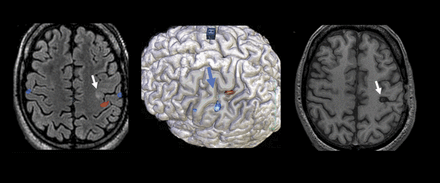

封面图片:fMRI显示左侧初级运动皮层局灶性皮质发育不良2型耐药性癫痫患者手术前(左和中间的照片)。正确的图像显示的完整切除病变术后。程式化的凯特林阿曼•兰姆、数字多媒体/图形协调员。看到页面e11